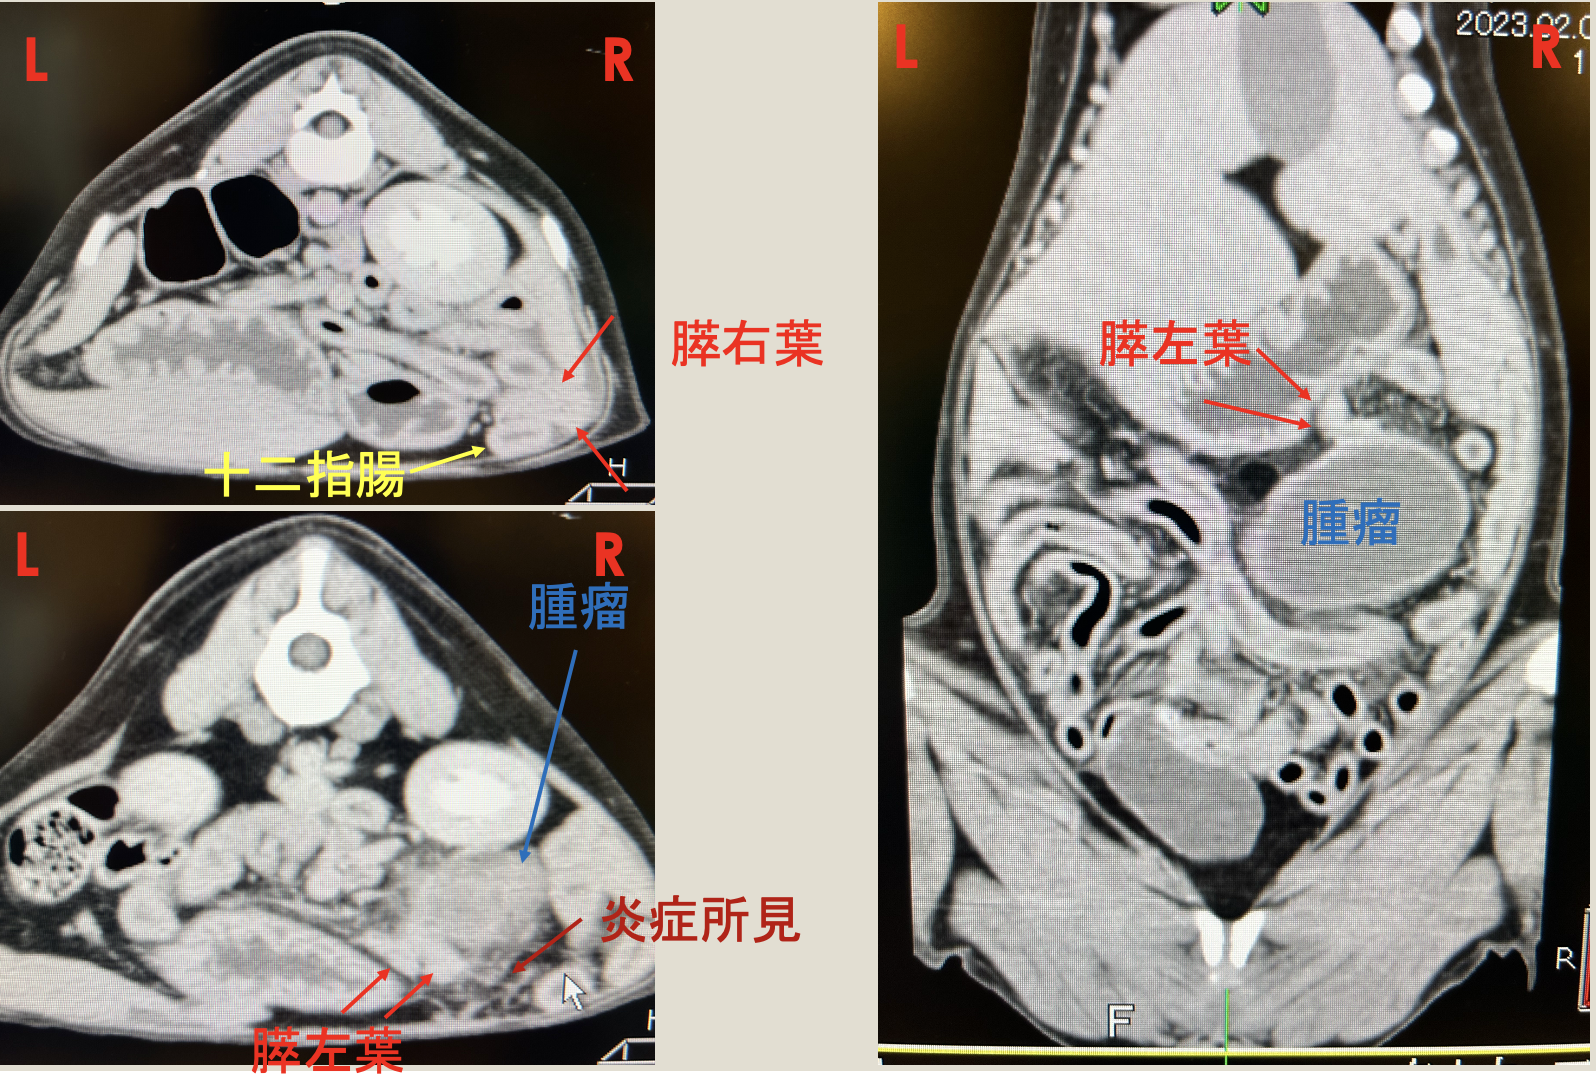

膵嚢胞

膵嚢胞とは、膵臓内またはその周囲に液体がたまり袋状(嚢胞)になる病変のことです。真性嚢胞、仮性嚢胞、膿瘍性嚢胞、嚢胞性腫瘍に分類されます。犬では、膵炎後の仮性嚢胞が一般的です

超音波検査、CT検査より膵臓周囲に腫瘤

開腹手術により膵嚢胞を切除した